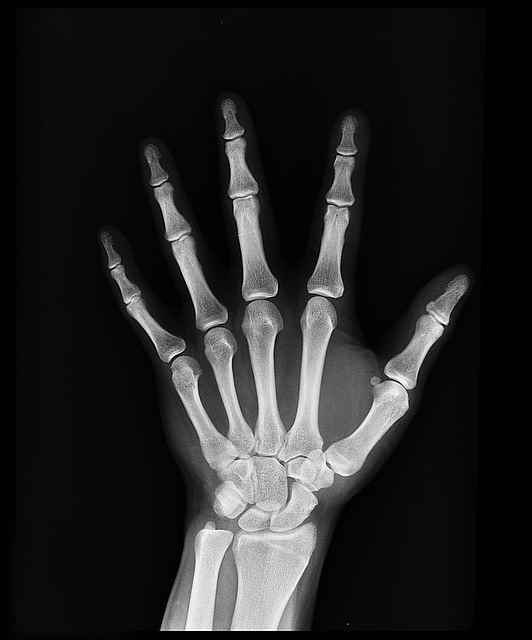

8. 관절 기형

관절염의 진행 단계에서, 장기간의 염증과 관절 구조의 손상은 돌이킬 수 없는 관절 기형으로 이어질 수 있습니다. 이러한 기형은 관절 정렬 불량, 뼈 스퍼스, 그리고 관절 모양의 변화를 포함할 수 있고, 그로 인해 심각한 기능 장애와 장애가 발생할 수 있습니다.